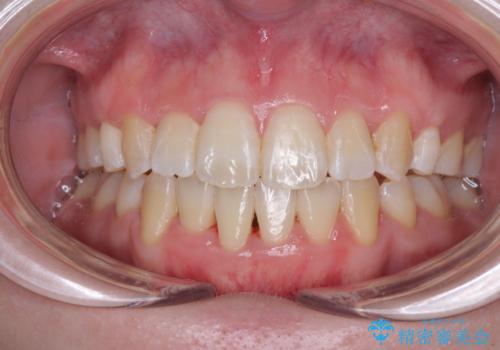

[ 前歯開咬 ] 前歯が噛んでいない マウスピース矯正治療

担当医 大元洋佑